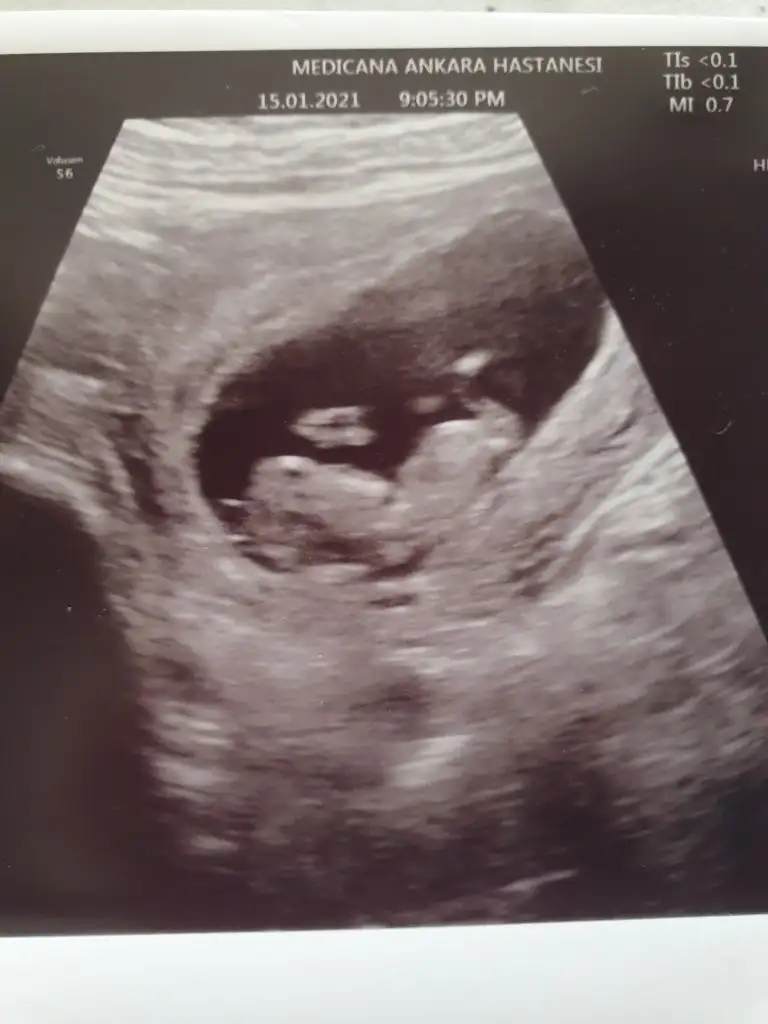

dr soylemeden siz gorun genital nub teorisi ( bebegin cinsiyeti)

Tahminde bulunabilirmisiniz

Mrb ıkra meyra bebeğim 7 haftalik tahmin edebilirmisin acaba